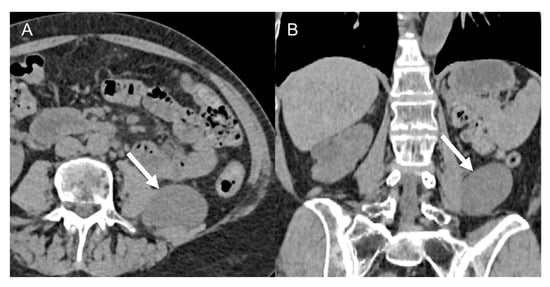

- The beak (claw) sign: when a mass deforms the edge of an adjacent organ into a “beak” shape, it is likely that the mass arises from that organ (e.g., a notch or an infiltration of the renal hilum, suggests a kidney origin of the tumor in the differential diagnosis between LPS and angiomyolipoma (Figure 7) [11,46]).

Figure 7. Renal angiomyolipoma in 62-year-old man. Axial CT images on the pre-contrast (A), arterial (B), and venous (C) phases and coronal venous (D) phase show a 4.5 cm heterogenous adipose lesion deforming the edge of the right kidney with a “beak” shape appearance (claw sign, arrows). - The embedded organ sign: when there is intimate contact between the mass and the organ of origin, a desmoplastic reaction and sometimes ulcerations are observed (positive sign). On the contrary, a moldable, compressed organ will be deformed into a crescent shape (negative sign). The latter is useful for example in the differential diagnosis between RP leiomyosarcoma and primitive inferior cava leiomyosarcoma [36,46].